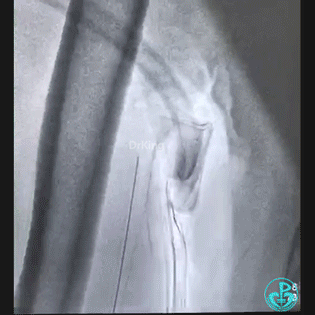

桡动脉鞘进JR 4.0指引导管,送入Sion,沿Sion送入2.5mm球囊,球囊越过穿刺导丝到达远端,6atm“打起来”后回撤,导丝被球囊带回来到指引导管口附近。

持续球囊锚定导丝调整指引导管角度,对准后回拉球囊,将导丝带入指引导管内,最后连同指引导管一起成功拉出。